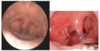

En 22-årig kvinde henvender sig til sin praktiserende læge med synkesmerter gennem 3 dage og feber. Her til morgen har hun målt sin temperaturen var til morgen 39,1 oC. Hun har drukket og spist sparsomt siden i går og er nu lettere alment utilpas. Der er ingen vejrtrækningsproblemer. Hun er tidligere i det væsentligste rask. For et par år siden oplevede hun dog symptomer der ligner de aktuelle.

Ved inspektion af svælget ses fund som i nedenstående figur. Der er hævede og ømme lymfeknuder bag kæbevinklen.

I: Hvad er den mest sandsynlige årsag til patientens symptomer (diagnose)?

Akut tonsillit (1)

Synkesmerter, feber, hævede angulære lymfeknuder samt hvide belægninger er klassiske symptomer på en akut bakteriel tonsillit.

En 22-årig kvinde henvender sig til sin praktiserende læge med synkesmerter gennem 3 dage og feber. Her til morgen har hun målt sin temperaturen var til morgen 39,1 oC. Hun har drukket og spist sparsomt siden i går og er nu lettere alment utilpas. Der er ingen vejrtrækningsproblemer. Hun er tidligere i det væsentligste rask. For et par år siden oplevede hun dog symptomer der ligner de aktuelle.

Ved inspektion af svælget ses fund som i nedenstående figur. Der er hævede og ømme lymfeknuder bag kæbevinklen.

II: Hvilke differentialdiagnoser overvejer du?

- Mononucleosis infectiosa (1)

- Pharyngitis acuta (1)

En 22-årig kvinde henvender sig til sin praktiserende læge med synkesmerter gennem 3 dage og feber. Her til morgen har hun målt sin temperaturen var til morgen 39,1 oC. Hun har drukket og spist sparsomt siden i går og er nu lettere alment utilpas. Der er ingen vejrtrækningsproblemer. Hun er tidligere i det væsentligste rask. For et par år siden oplevede hun dog symptomer der ligner de aktuelle.

Ved inspektion af svælget ses fund som i nedenstående figur. Der er hævede og ømme lymfeknuder bag kæbevinklen.

IIl. Beskriv Centor kriterierne

Centor-kriterier

- Feber over 38,5° C (1)

- Belægninger på tonsillerne (1)

- Angulær lymfadenit (1)

- Ikke hoste (1)

En 22-årig kvinde henvender sig til sin praktiserende læge med synkesmerter gennem 3 dage og feber. Her til morgen har hun målt sin temperaturen var til morgen 39,1 oC. Hun har drukket og spist sparsomt siden i går og er nu lettere alment utilpas. Der er ingen vejrtrækningsproblemer. Hun er tidligere i det væsentligste rask. For et par år siden oplevede hun dog symptomer der ligner de aktuelle.

Ved inspektion af svælget ses fund som i nedenstående figur. Der er hævede og ømme lymfeknuder bag kæbevinklen.

IV. Skal denne patient have foretaget en Strep A test i henhold til Centor criterierne for at få ordineret penicillin?

Ja

Begrundelse:

- Fordi hun opfylder alle 4 kriterier

- Ved op til 2 kriterier til stede: sandsynlighed for GAS 15 % eller lavere. Konsekvens: ingen antigenhurtigtest eller antibiotika

- Ved 3 eller 4 kriterier opfyldt (10-20 % af alle med ondt i halsen): sandsynlighed for GAS 32-56 %. Unge mellem 15-17 år kan behandles med antibiotikum uden yderligere test.

- Andre får lavet en antigentest

(0-1 point)

En 22-årig kvinde henvender sig til sin praktiserende læge med synkesmerter gennem 3 dage og feber. Her til morgen har hun målt sin temperaturen var til morgen 39,1 oC. Hun har drukket og spist sparsomt siden i går og er nu lettere alment utilpas. Der er ingen vejrtrækningsproblemer. Hun er tidligere i det væsentligste rask. For et par år siden oplevede hun dog symptomer der ligner de aktuelle.

Ved inspektion af svælget ses fund som i nedenstående figur. Der er hævede og ømme lymfeknuder bag kæbevinklen.